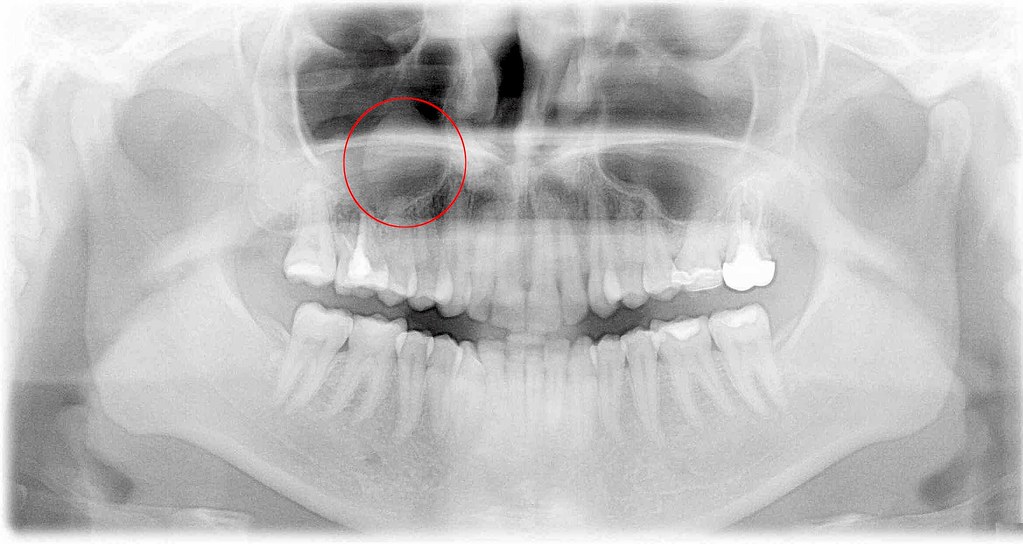

A teratoma is a rare type of germ cell tumor that may contain immature or fully formed tissue, including teeth, hair, bone and muscle. Dentigerous cysts are caused by a buildup of fluid over the top of an unerupted tooth. For example, wisdom teeth are often buried;

In addition, you will learn how much the surgery to remove a tooth cyst costs. Web what is a cyst with hair and teeth? Web dermoid cysts happen when ectodermal germ cells—which go on to form structures on the outer layers of our body, like skin, oil or sweat glands, hair, teeth, etc.—more or less get stuck in the.